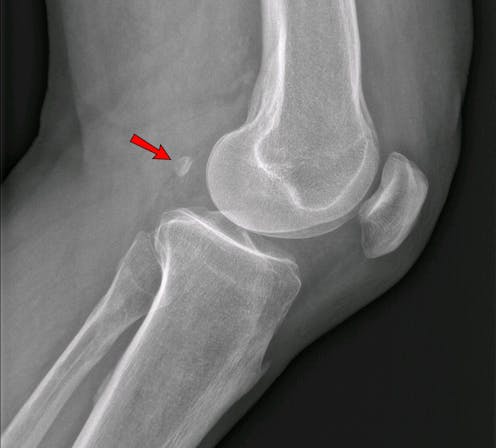

Scientists in the UK recently reported that a bone that was thought to be lost to evolution is making a comeback. The little bone, known as the fabella (little bean), is found at the back of the knee – if it is found at all. The scientists discovered that people were nearly three-and-a-half times more likely to have the bone in 2000 than in 1900. Its exact purpose, however, remains a mystery.